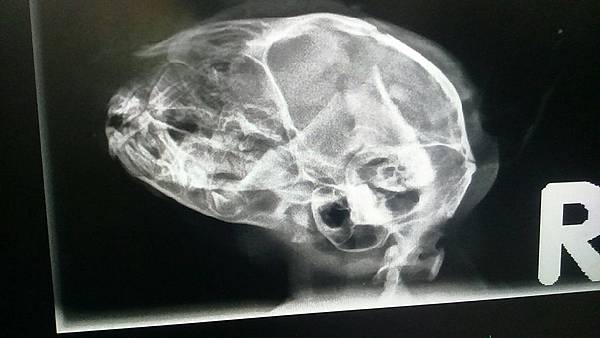

被狗狗咬到頭部,牙齒咬破了頭骨

另一側也有凹洞

頭部X光

這孩子因為被狗咬傷,頭骨多處破裂粉碎

腦血腫腦壓過高,一直呈現低頭狀態